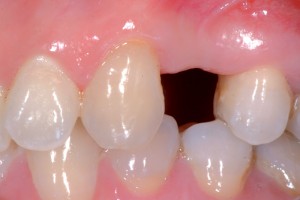

La paziente di 45 anni si presenta all’osservazione con sintomatologia localizzata a carico di 24 e riferisce di aver avuto episodi acuti in passato. L’elemento 24 si presenta trattato endodonticamente, con perno endocanalare in falsa strada, e corona in metallo-ceramica; si presenta inoltre dolente alla masticazione, alla palpazione e alla percussione, mobile (con mobilità di grado 2), e si evidenziano una tumefazione in corrispondenza della gengiva vestibolare e una ampia rarefazione peri-apicale (Figg. 2, 3).

- Fig. 2

- Fig. 3